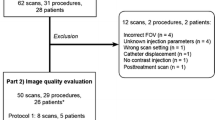

The purpose of this study was to determine whether rotational C-arm computed tomography (CT) allows visualization of liver metastases and adds relevant information for radioembolization (RE) treatment planning. Technetium angiography, together with C-arm CT, was performed in 47 patients to determine the feasibility for RE. C-arm CT images were compared with positron emission tomography (PET)/CT images for the detection of liver tumors. The images were also rated according one of the following three categories: (1) images that provide no additional information compared with DSA alone; (2) images that do provide additional information compared with DSA; and (2) images that had an impact on eligibility determination for and planning of the RE procedure. In all patients, 283 FDG-positive liver lesions were detected by PET. In venous contrast-phase CT, 221 (78.1%) and 15 (5.3%) of these lesions were either hypodense or hyperdense, respectively. In C-arm CT, 103 (36.4%) liver lesions were not detectable because they were outside of either the field of view or the contrast-enhanced liver segment. Another 25 (8.8%) and 98 (34.6%) of the liver lesions were either hyperdense or presented primarily as hypodense lesions with a rim enhancement, respectively. With PET/CT as the standard of reference, venous CT and C-arm CT failed to detect 47 (16.6%) and 57 (20.1%) of all liver lesions, respectively. For RE planning, C-arm CT provided no further information, provide some additional information, or had an impact on the procedure in 20 (42.5%), 15 (31.9%) and 12 (25.6%) of patients, respectively. We conclude that C-arm CT may add decisive information in patients scheduled for RE.

Diagnostic angiography, C-arm CT, and PET/CT were performed in 47 patients (mean age 61.9 ± 11.1 years; 27 female) for the eligibility and feasibility of RE therapy. Before the examination, all patients gave informed consent to undergo the comprehensive diagnostic work-up. Patient disease included metastases of colorectal (n = 26), pancreatic (n = 2), or breast cancer (n = 8); cholangiocellular carcinoma (n = 3); unknown primary cancer (n = 2); melanoma (n = 2); or ovarian, uterus, adrenal gland, or hepatocellular carcinoma (HCC) (n = 1 each).

In all 47 patients, a total of 283 liver lesions with an SUV >2.5 were identified by PET. Venous contrast-enhanced CT, detected 221 (78.0%) and 15 (5.3%) of these lesions as either hypodense or hyperdense lesions, respectively. Correspondingly, 47 (16.6%) PET-positive liver lesions were not seen on venous contrast-phase CT images (Fig. 1). One hundred three of the 283 (36.4%) liver lesions detected by PET/CT were found to be located outside the field of view or the contrast-enhanced liver segments of the C-arm CT images. Of the remaining 180 lesions, 25 (8.8%) and 98 (34.6%) were identified as hyperdense lesions or hypodense lesions with a characteristic hyperattenuating rim, respectively. Although located in the contrast-enhanced liver segment, the remaining 57 (20.1%) liver lesions could not be seen on the C-arm CT images.

PET serves as the “gold standard” for the detection of liver lesions. Hypodense and hyperdense liver lesions, 71 and 5.3%, respectively, were detected by venous contrast-phase CT. Of all lesions, 8.8% were hyperdense in C-arm CT, and 34.6% were hypodense, showing a characteristic rim enhancement. Of the liver lesions, 16.6 and 20.1%, respectively, were detected neither by conventional CT nor by C-arm CT. Another 36.4% of all lesions were outside the field of view or the contrast-enhanced liver parenchyma in C-arm CT images

According to our rating system, C-arm CT provided no additional information compared with DSA in 20 of 47 (42.5%) patients and provided additional information in another 15 (31.9%) patients. In 5 patients, it could be demonstrated by C-arm CT that the main tumor load could not be reached by the actual catheter position (n = 4) or had no tumor blush at all (n = 1). The suspicion of an early portal-venous shunting or a small arterial-venous fistula was raised from C-arm CT images in another 2 patients. Contrast-enhancement outside the liver was detected in the wall of the gall bladder or in the stomach in 3 and 2 patients, respectively. Therefore, information achieved by C-arm CT led to a change in therapy planning or eligibility in 12 (25.6%) patients.